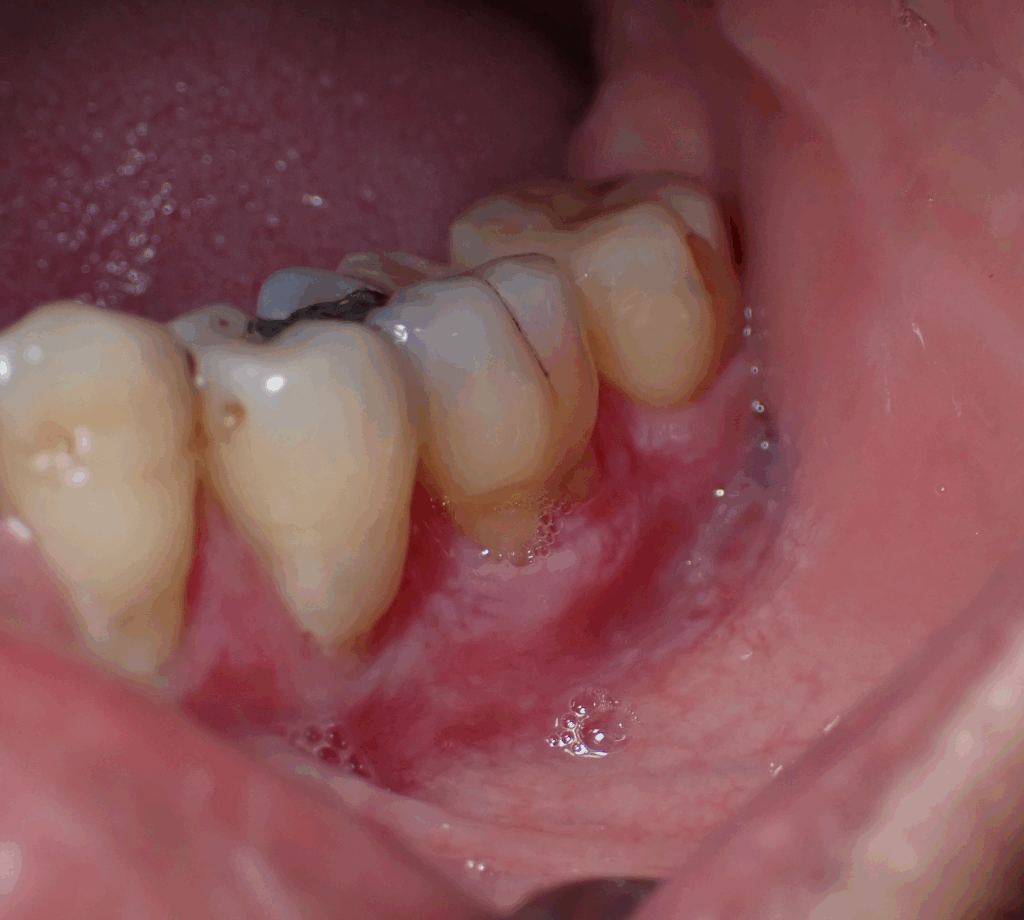

Less severe yet clinically significant forms, such as plasma-cell gingivitis (Figure 3) and oral allergy syndrome (OAS), are usually reversible once the allergen, often a flavoring or food protein, is identified and removed [10].

Figure 3. Picture of patient with biopsy proven Plasma Cell Gingivitis